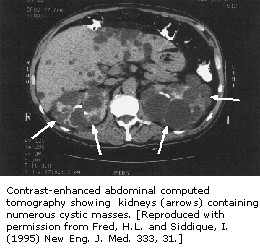

![]() | ![]() |

| 鐮狀細胞性貧血導致顱骨改變 | 鐮狀細胞性貧血導致腦改變 |

鐮狀細胞性貧血的患兒較容易患有雙球菌肺炎。有時也會出現腎臟、脾臟或腦部供血不足的情況,從而造成這些器官受損。